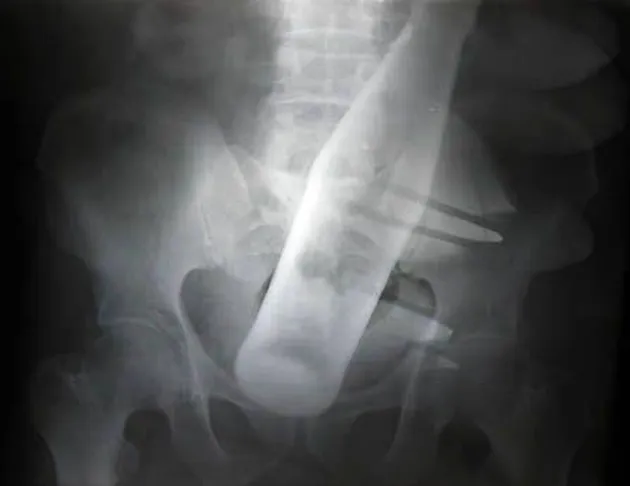

Seorang pria berusia 60 tahun mengaku jika ada maling yang mencoba memasukkan botol Coca Cola ke dalam anusnya. Ew. Beruntung dokter akhirnya bisa mengeluarkan botol tersebut dengan beberapa alat medis yang dimilikinya.